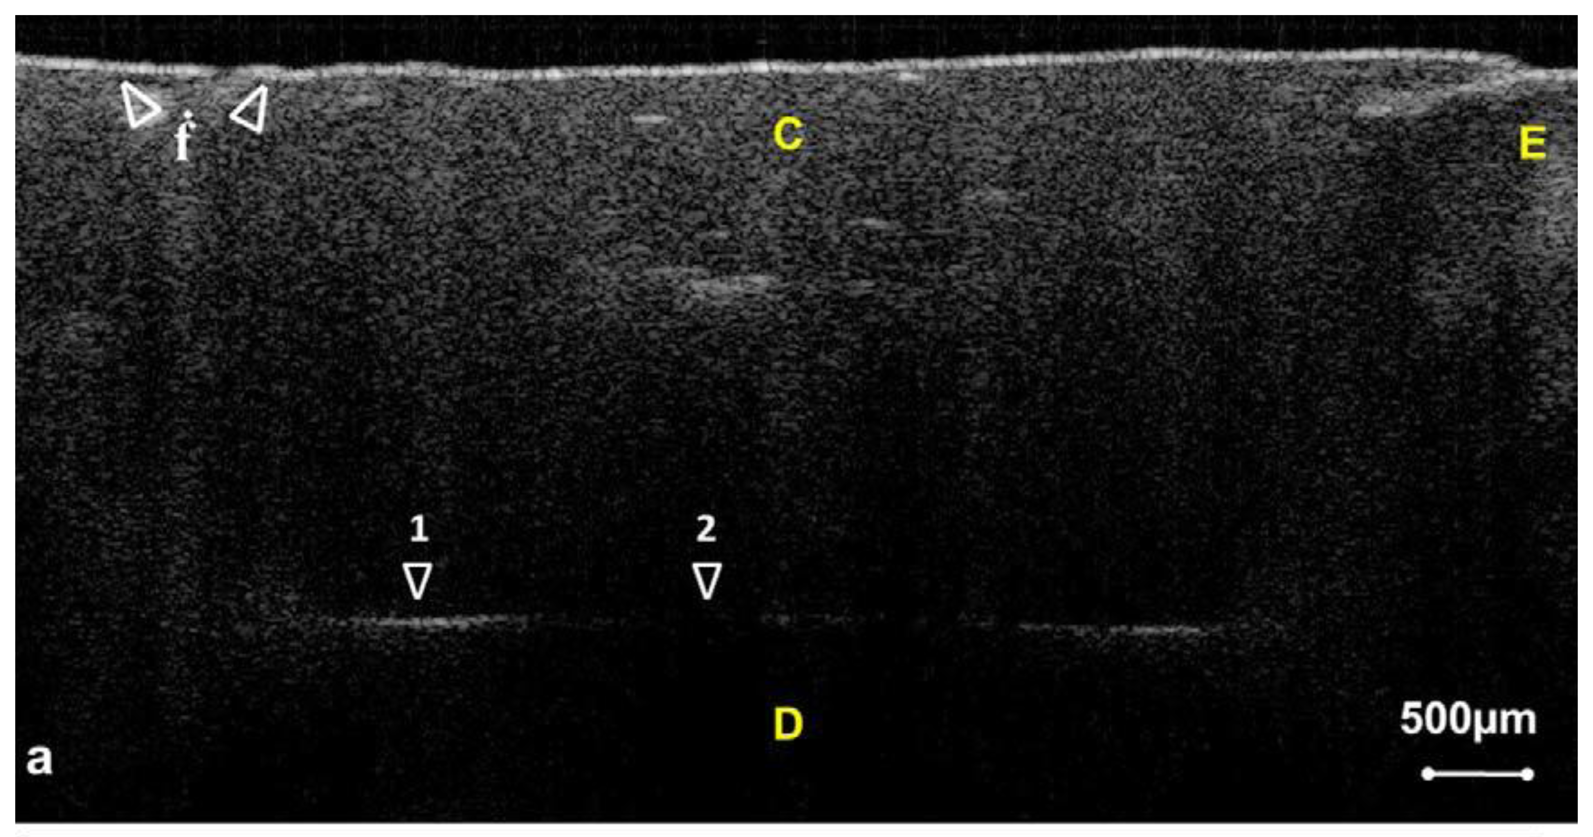

Periodontitis is one of the major chronic infectious diseases in the oral cavity. The prevalence of periodontitis is more than 50% among the population [77,78]. The WHO revealed that tooth loss resulting from severe periodontitis was found in 5%–15% of most worldwide populations in 2003 [79]. Additionally, recent studies have indicated that certain correlations between periodontitis and various systemic diseases exist [80–82]. Colston et al. were the first group to apply OCT in the diagnosis of periodontal disease [83,84]. They took in vitro images of dental and periodontal tissues from a young porcine model and compared these images to histological sections. Feldchteine et al. demonstrated epithelium and lamina propria of gingival mucosa [45]. However, the epithelium and lamina propria were not well differentiated because of the physical limitation. Baek et al. represented OCT images of periodontal ligaments during orthodontic movement of rat (Figure 11) [85]. Hsieh et al. demonstrated subgingival calculus in vitro. Tooth with subgingival calculus covered with 0.8 mm porcine gingiva was measured (Figure 12). Subgingival calculus is one of the pathogenetic factors of periodontal disease, so it is important to remove the residual subgingival calculus [28]. The refractive indices of enamel, dentin, cementum, and calculus were also measured as 1.625 ± 0.024, 1.534 ± 0.029, 1.570 ± 0.021, and 2.097 ± 0.094, respectively. The refractive indices help clinicians to distinguish calculus from normal tissues rapidly and correctly. With the aid of OCT, early detection of periodontal disease and monitoring of periodontal treatment could be very helpful.